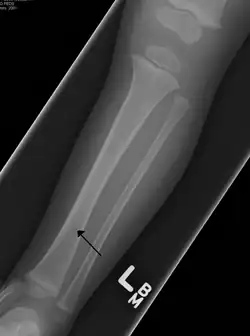

A toddler's fracture

Toddler's fractures are bone fractures of the distal (lower) part of the shin bone (tibia) in toddlers (aged 9 months-3 years) and other young children (less than 8 years).[1] The fracture is found in the distal two thirds of the tibia in 95% of cases,[1] is undisplaced and has a spiral pattern. It occurs after low-energy trauma, sometimes with a rotational component.

Typical symptoms include pain, refusing to walk or bear weight and limping -bruising and deformity are absent. On clinical examination, there can be warmth and swelling over the fracture area, as well as pain on bending the foot upwards (dorsiflexion). The initial radiographical images may be inconspicuous (a faint oblique line) and often even completely normal.[3] After 1–2 weeks however, callus formation develops. The condition can be mistaken for osteomyelitis, transient synovitis or even child abuse. Contrary to CAST fractures, non-accidental injury typically affect the upper two-thirds or midshaft of the tibia.